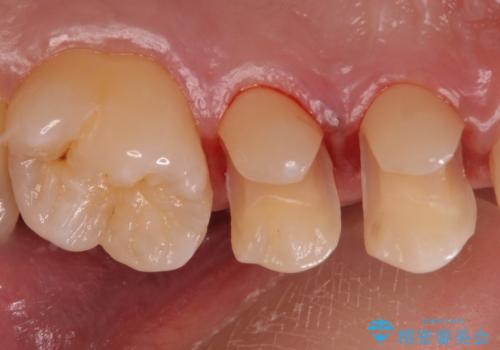

- 外から見える範囲の銀歯のやり替えをご希望で来院されました。

セラミックインレーでの治療となります。